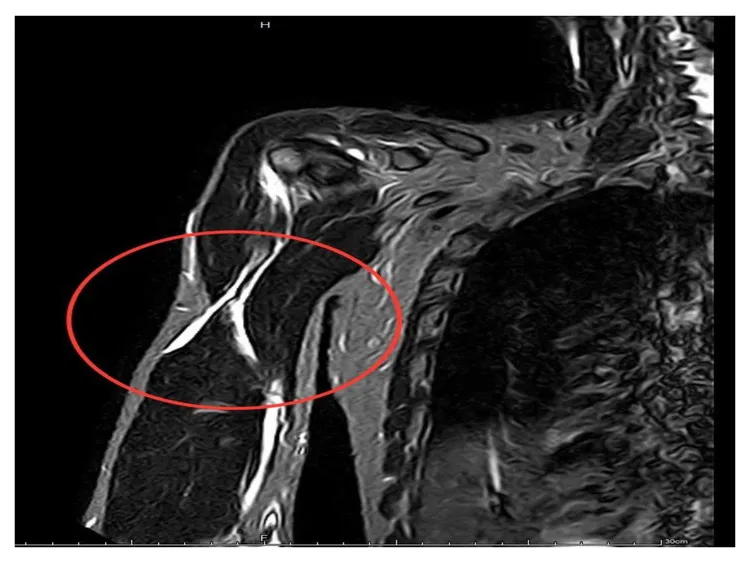

核磁共振(MRI)影像顯示,病患的肱二頭肌長頭斷裂(紅圈處)。院方提供